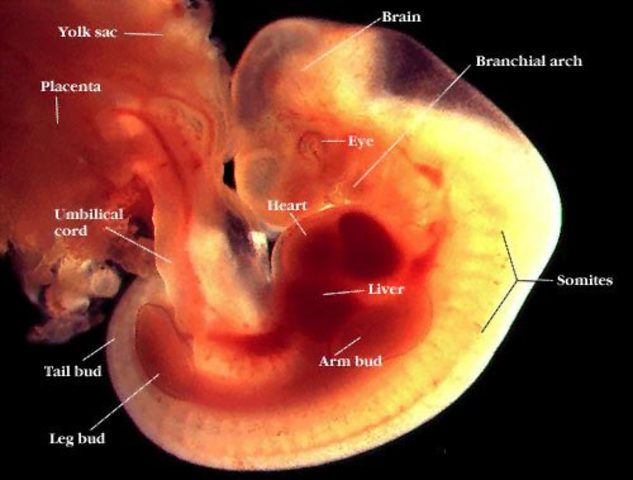

• Semana 3

Semana 3

El embrión mide aproximadamente 1,25 mm

Tiene 3 capas de células que formarán la cabeza.

Para esta semana al embrión ya le comienza a latir el corazón, lo que provoca que todo su cuerpo se nutra en la ausencia del cerebro.

Los ojos ya tienen un color diferente al resto del cuerpo.

Se comienza a forma el primer sistema en el embrión: el nervioso.

Los 23 cromosomas del óvulo se han unido a los 23 cromosomas del espermatozoide. Se establece el sexo del bebé y sus características físicas y mentales.

• Semana 4

Semana 4

Se comienzan a formar las extremidades del cuerpo así como la nariz y las cavidades para el tubo digestivo y pulmones.

Se forma el primer esbozo del sistema nervioso, el cual dara nacimiento al cerebro, la médula espinal y los nervios.

Las 3 capas anteriormente mencionadas forman lo siguiente.

1ra capa: Sistema respiratorio y digestivo

2da capa: Huesos, músculos, cartílagos, organos sexuales, riñones y sistema circulatorio.

3ra capa: Piel, pelo, sistema nervioso

Ahora mide 4mm